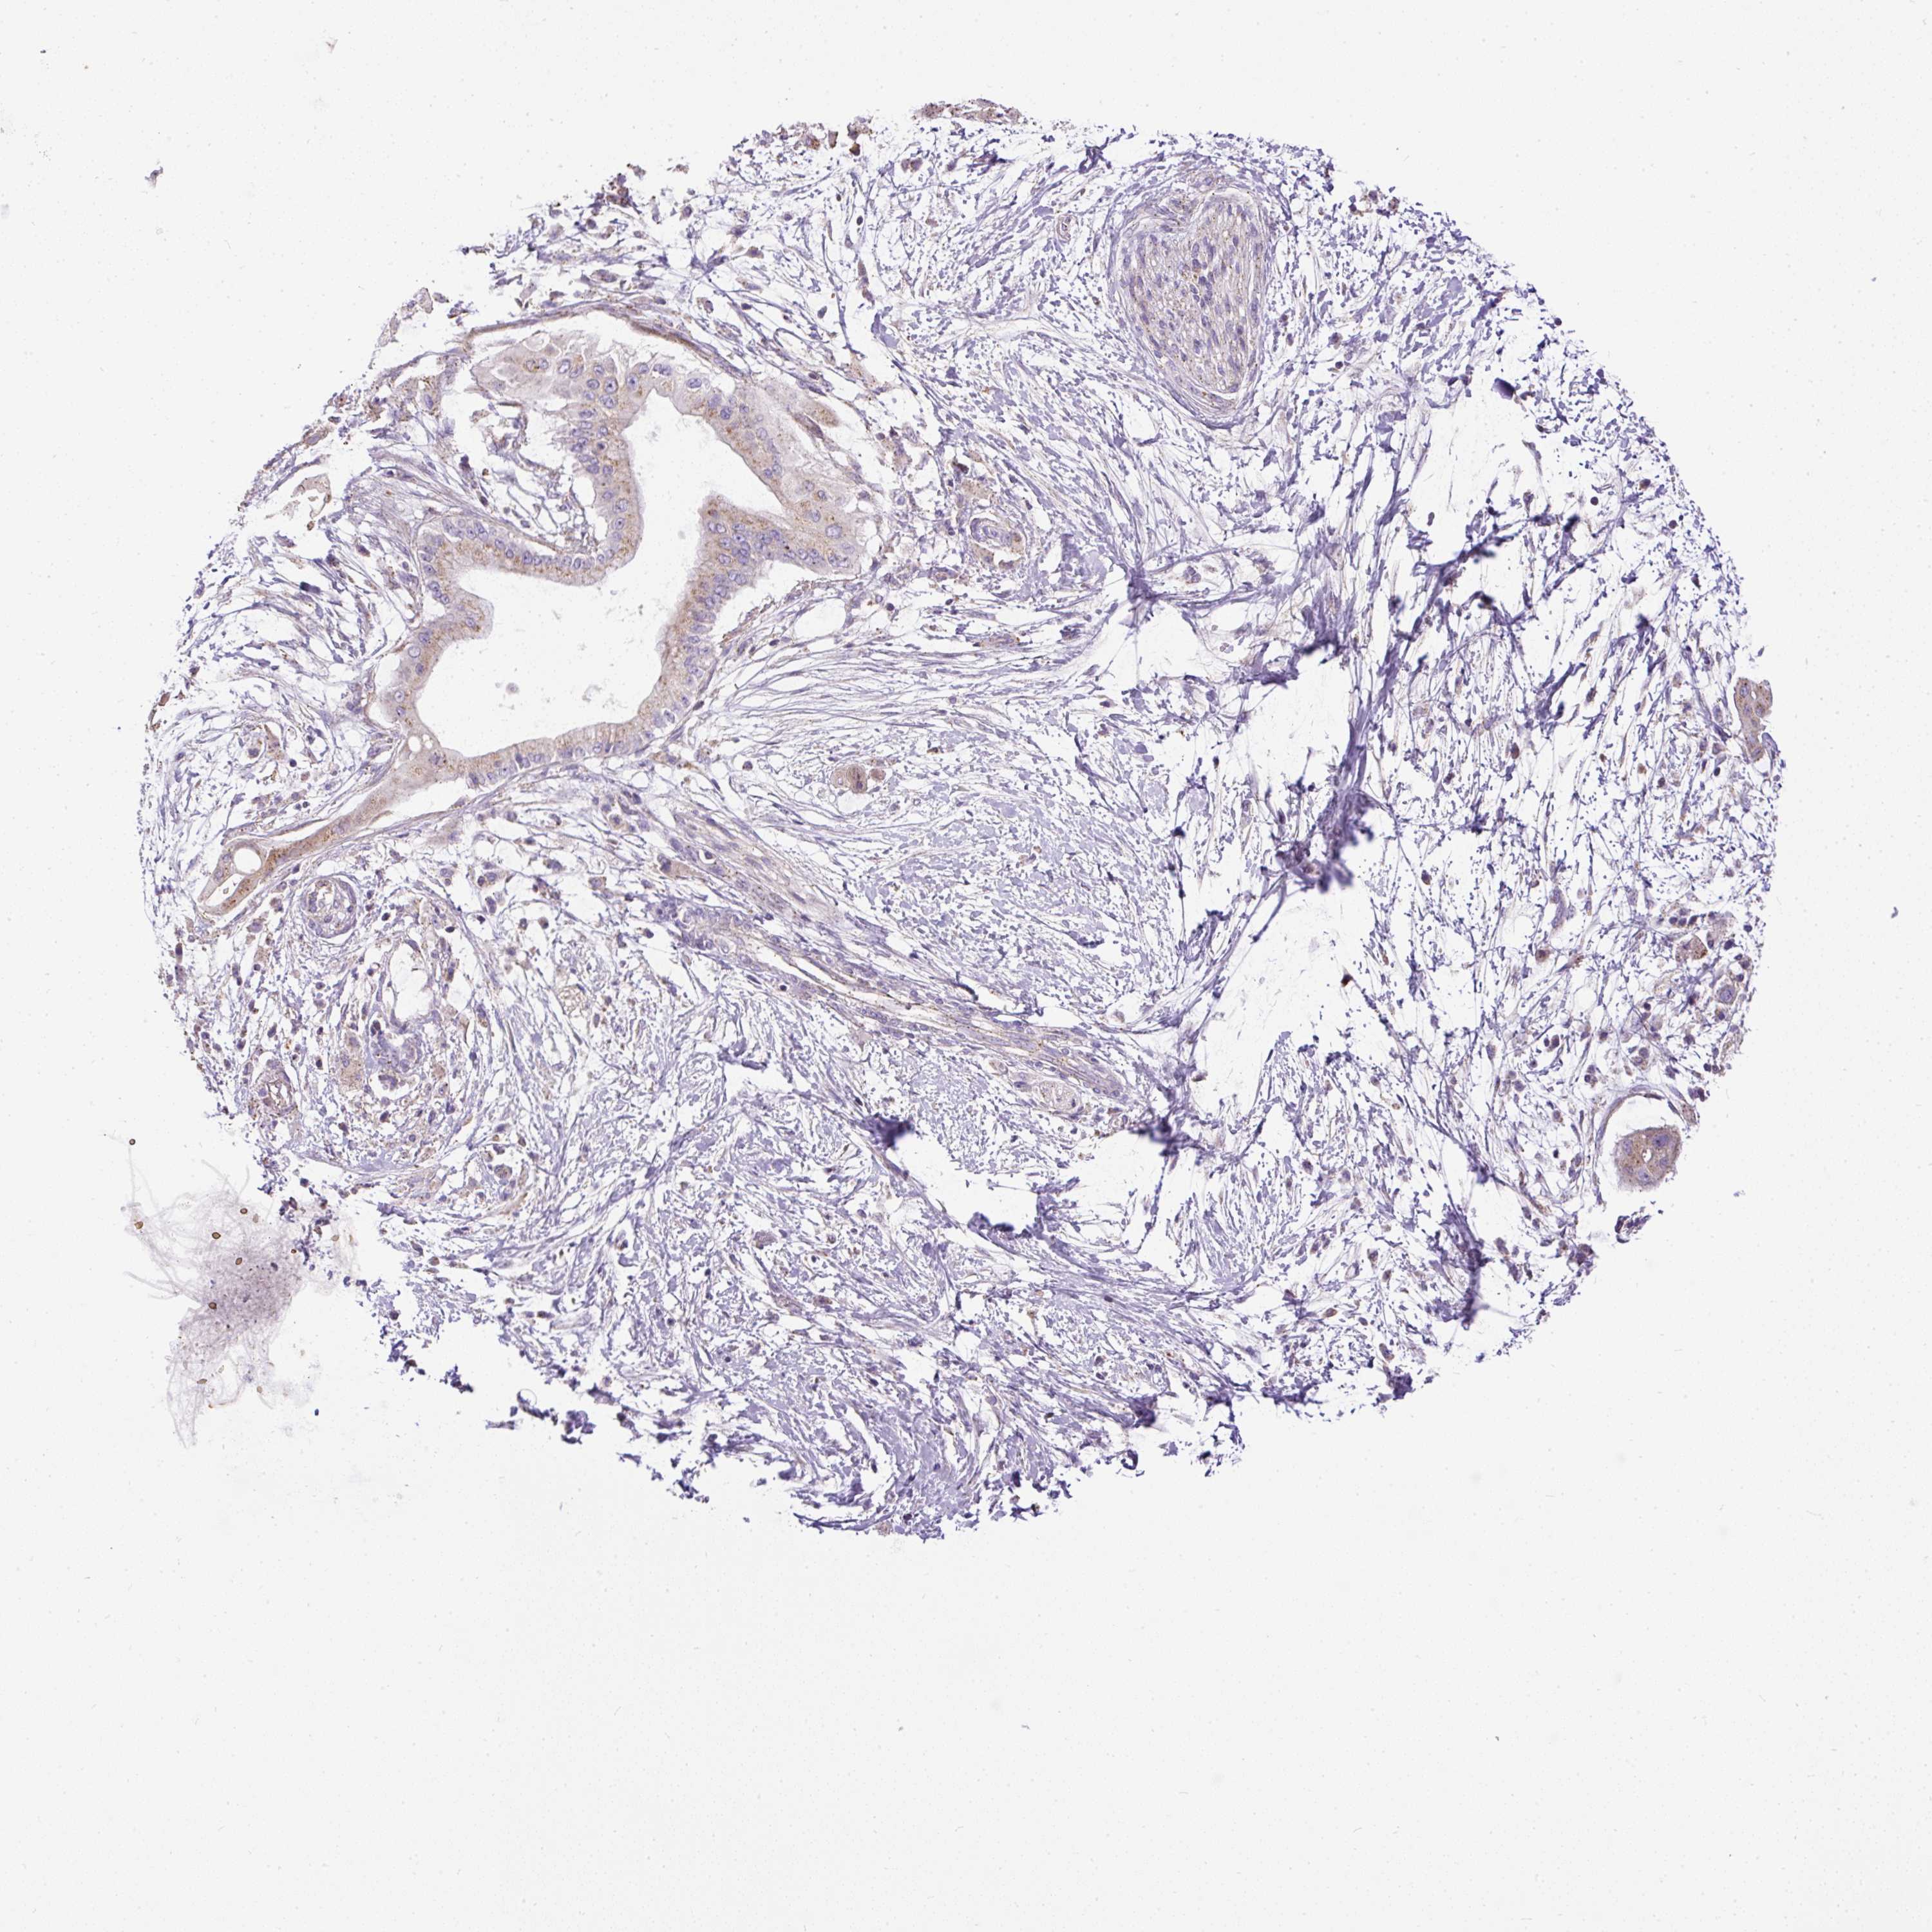

PANCREATIC CANCER - Protein expressioni

A mouse-over function shows sample information and annotation data. Click on an image to view it in a full screen mode. Samples can be filtered based on level of antibody staining by selecting one or several of the following categories: high, medium, low and not detected. The assay and annotation is described here.

Note that samples used for immunohistochemistry by the Human Protein Atlas do not correspond to samples in the TCGA dataset.

Antibody stainingi

Antibody staining in the annotated cell types in the current human tissue is reported as not detected, low, medium, or high, based on conventional immunohistochemistry profiling in selected tissues. This score is based on the combination of the staining intensity and fraction of stained cells.

Each image is clickable and will lead to virtual microscopy that enables deeper exploration of all samples and also displays staining intensity scores, fraction scores and subcellular localization as well as patient and tissue information for each sample.

Antibody HPA044633

Antibody HPA054859

Staining

High

Medium

Low

Not detected

Intensity

Strong

Moderate

Weak

Negative

Quantity

>75%

75%-25%

<25%

None

Location

Nuclear

Cytoplasmic/membranous

Cytoplasmic/membranous,nuclear

Adenocarcinoma, NOS